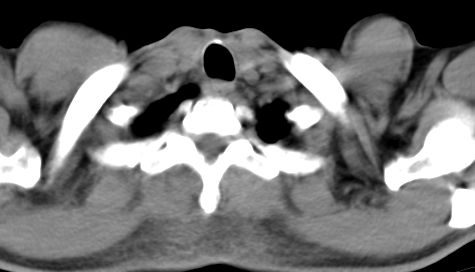

标题: CT10147:男、55岁,咯血10天,有结核病史。 [打印本页]

标题: CT10147:男、55岁,咯血10天,有结核病史。

左上周围型肺癌;伴纵膈淋巴结转移。

左上肺尖后段上面陈旧性结核,下面邻近左肺门旁可见软组织肿块影,与上肺v关系密切,左肺门及气管隆突下可见增大的淋巴结影,考虑1.左上肺ca(周围型)伴肺门纵隔内淋巴转移 2.左上肺陈旧性tb

左肺上叶中心性肺癌,伴肺门及纵隔淋巴结肿大